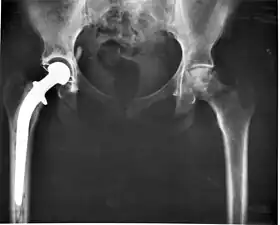

X-ray of a hip replacement

The modern total hip replacement was pioneered by Sir John Charnley, expert in tribology at Wrightington Hospital, in England in the 1960s.[10] He found that joint surfaces could be replaced by implants cemented to the bone. His design consisted of a stainless steel, one-piece femoral stem and head, and a polyethylene acetabular component, both of which were fixed to the bone using PMMA (acrylic) bone cement. For over two decades, the Charnley low-friction arthroplasty and its derivative designs were the most-used systems in the world. This formed the basis for all modern hip implants.

The Exeter hip replacement system (with a slightly different stem geometry) was developed at the same time. Since Charnley, improvements have been continuous in the design and technique of joint replacement (arthroplasty) with many contributors, including W. H. Harris, the son of R. I. Harris, whose team at Harvard pioneered uncemented arthroplasty techniques with the bone bonding directly to the implant.